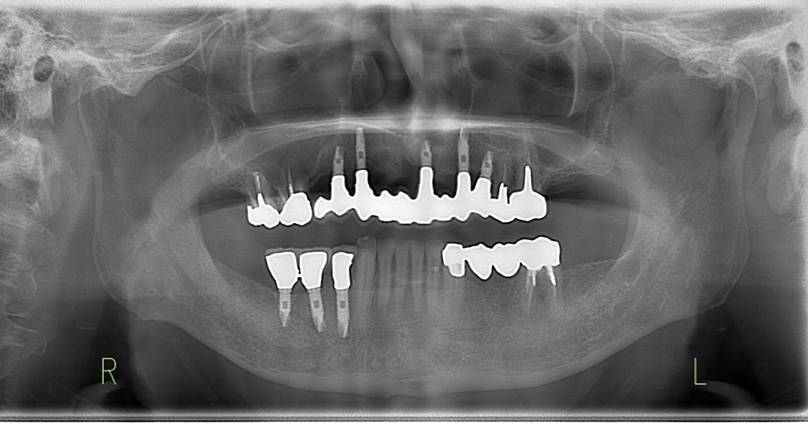

治療後。歯周病で失われた骨が回復しています。使用インプラントはスプラインツイストです。

上部構造装着後6年。ハイブリッドレジンを使用したため、少し艶がなくなってきました。上部構造の材料には金属、ハイブリッドレジン、セラミックなどがあります。セラミックはきれいですが欠けやすいため、最近はフルジルコニアを使っています。

下顎。12か月に一度メインテナンスをしています。

インプラント装着後6年。順調に経過しています。12か月毎のメインテナンスをしています。